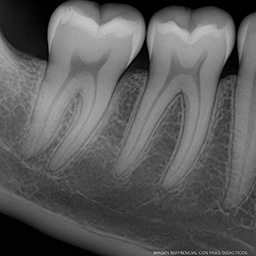

Ejemplo Radiografía Bitewing

imagen referencial con fines didácticos

La radiografía bitewing (también conocida como radiografía interproximal) es una técnica intraoral que permite visualizar las coronas de los dientes superiores e inferiores en una misma imagen. Es esencial para detectar caries entre los dientes, valorar el ajuste de restauraciones y realizar un seguimiento periodontal.